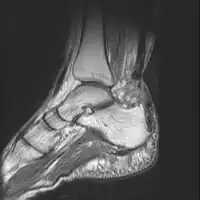

Imaging

Musculoskeletal ultrasonography can be used to determine the tendon thickness, character, and presence of a tear. It works by sending extremely high frequencies of sound through the body. Some of these sounds are reflected back off the spaces between interstitial fluid and soft tissue or bone. These reflected images can be analyzed and computed into an image. These images are captured in real time and can be very helpful in detecting movement of the tendon and visualising possible injuries or tears. This device makes it very easy to spot structural damages to soft tissues, and consistent method of detecting this type of injury. This imaging modality is inexpensive, involves no ionizing radiation and, in the hands of skilled ultrasonographers, may be very reliable.

MRI can be used to discern incomplete ruptures from degeneration of the Achilles tendon, and MRI can also distinguish between paratenonitis, tendinosis, and bursitis. This technique uses a strong uniform magnetic field to align millions of protons running through the body. These protons are then bombarded with radio waves that knock some of them out of alignment. When these protons return they emit their own unique radio waves that can be analysed by a computer in 3D to create sharp cross sectional image of the area of interest. MRI can provide unparalleled contrast in soft tissue for an extremely high quality photograph making it easy for technicians to spot tears and other injuries.

Achilles tendon rupture